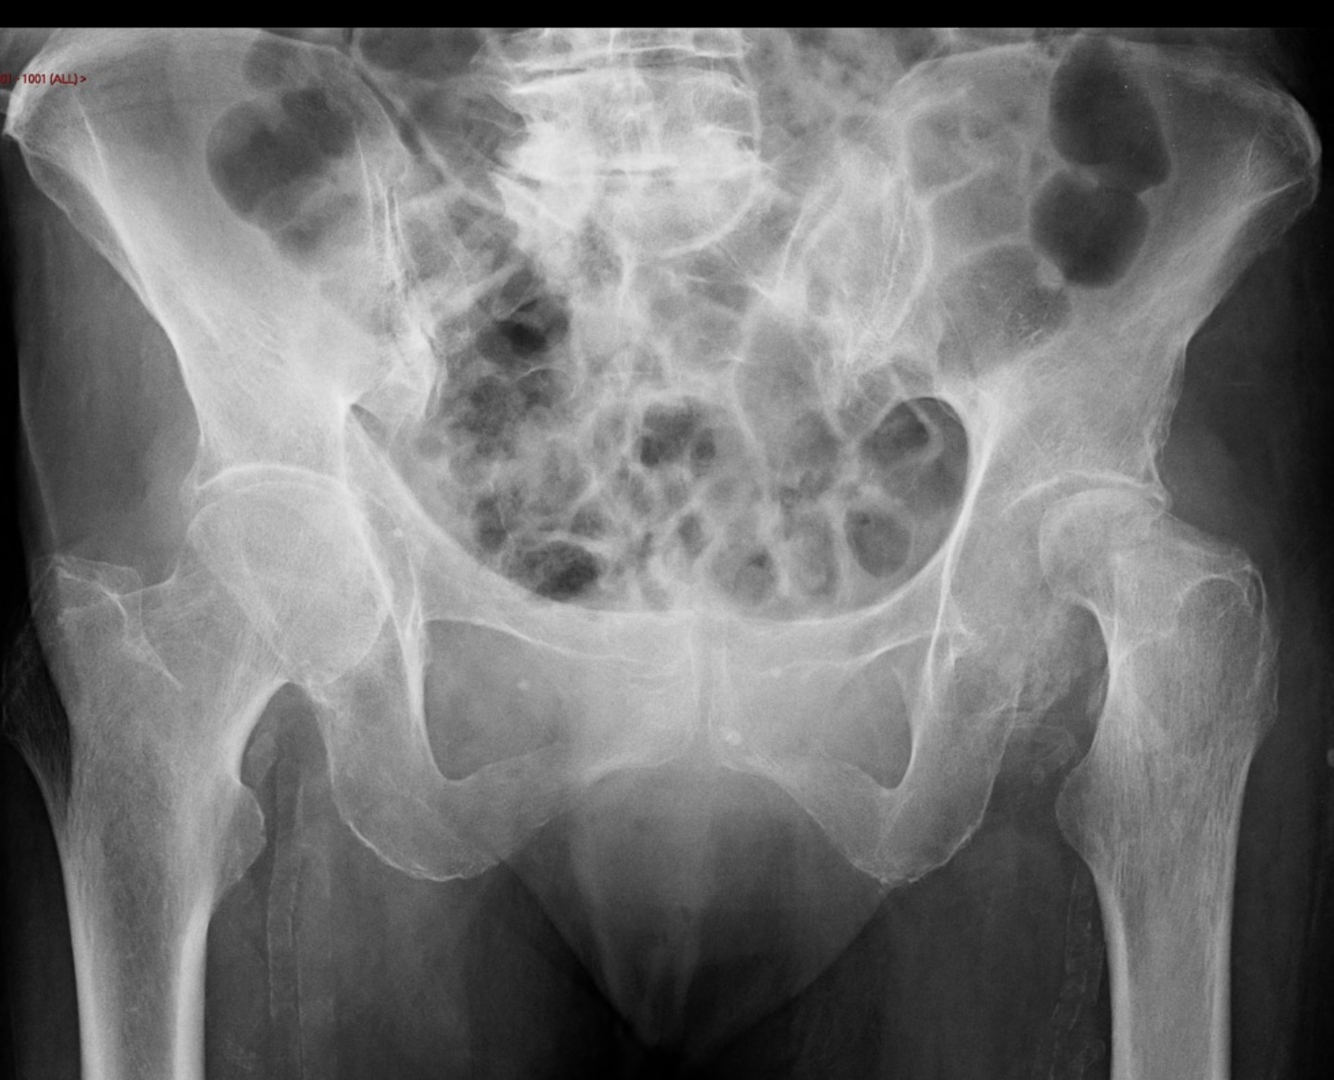

Hydroxyapatite deposition disease

Hydroxyapatite crystal deposition disease (HADD) is a disease of uncertain aetiology characterised by periarticular and intra-articular deposition of hydroxyapatite (HA) crystals.

HADD can affect other tendons of the body, such as the gluteus medius tendon, or along the femur, as well as at various sites of tendinous attachments (e.g. elbow, wrist, hand, knee, ankle, foot, and spine) 2.

Calcifications of varying sizes and shapes can involve the para-articular tendons, bursae, and capsule. The disease can be mono- or polyarticular.

Radiographic features

The specific appearance will vary based on the calcific stage, broken into the formative, resting and resorptive phases. The formative and resting phases will appear as round-to-ovoid calcification in the soft tissue with well-defined borders. The resorptive phase will appear ill-defined with a comet tail-like appearance. The resorptive may mimic a periosteal reaction 6.

Plain radiograph

It appears as homogeneous, round-to-ovoid calcification in the soft tissue with well-defined or ill-defined margins. The most characteristic lesions are seen in the shoulder with supraspinatus and biceps tendon involvement, adjacent to the greater tubercle and the glenoid tubercle, respectively, where these tendons attach.